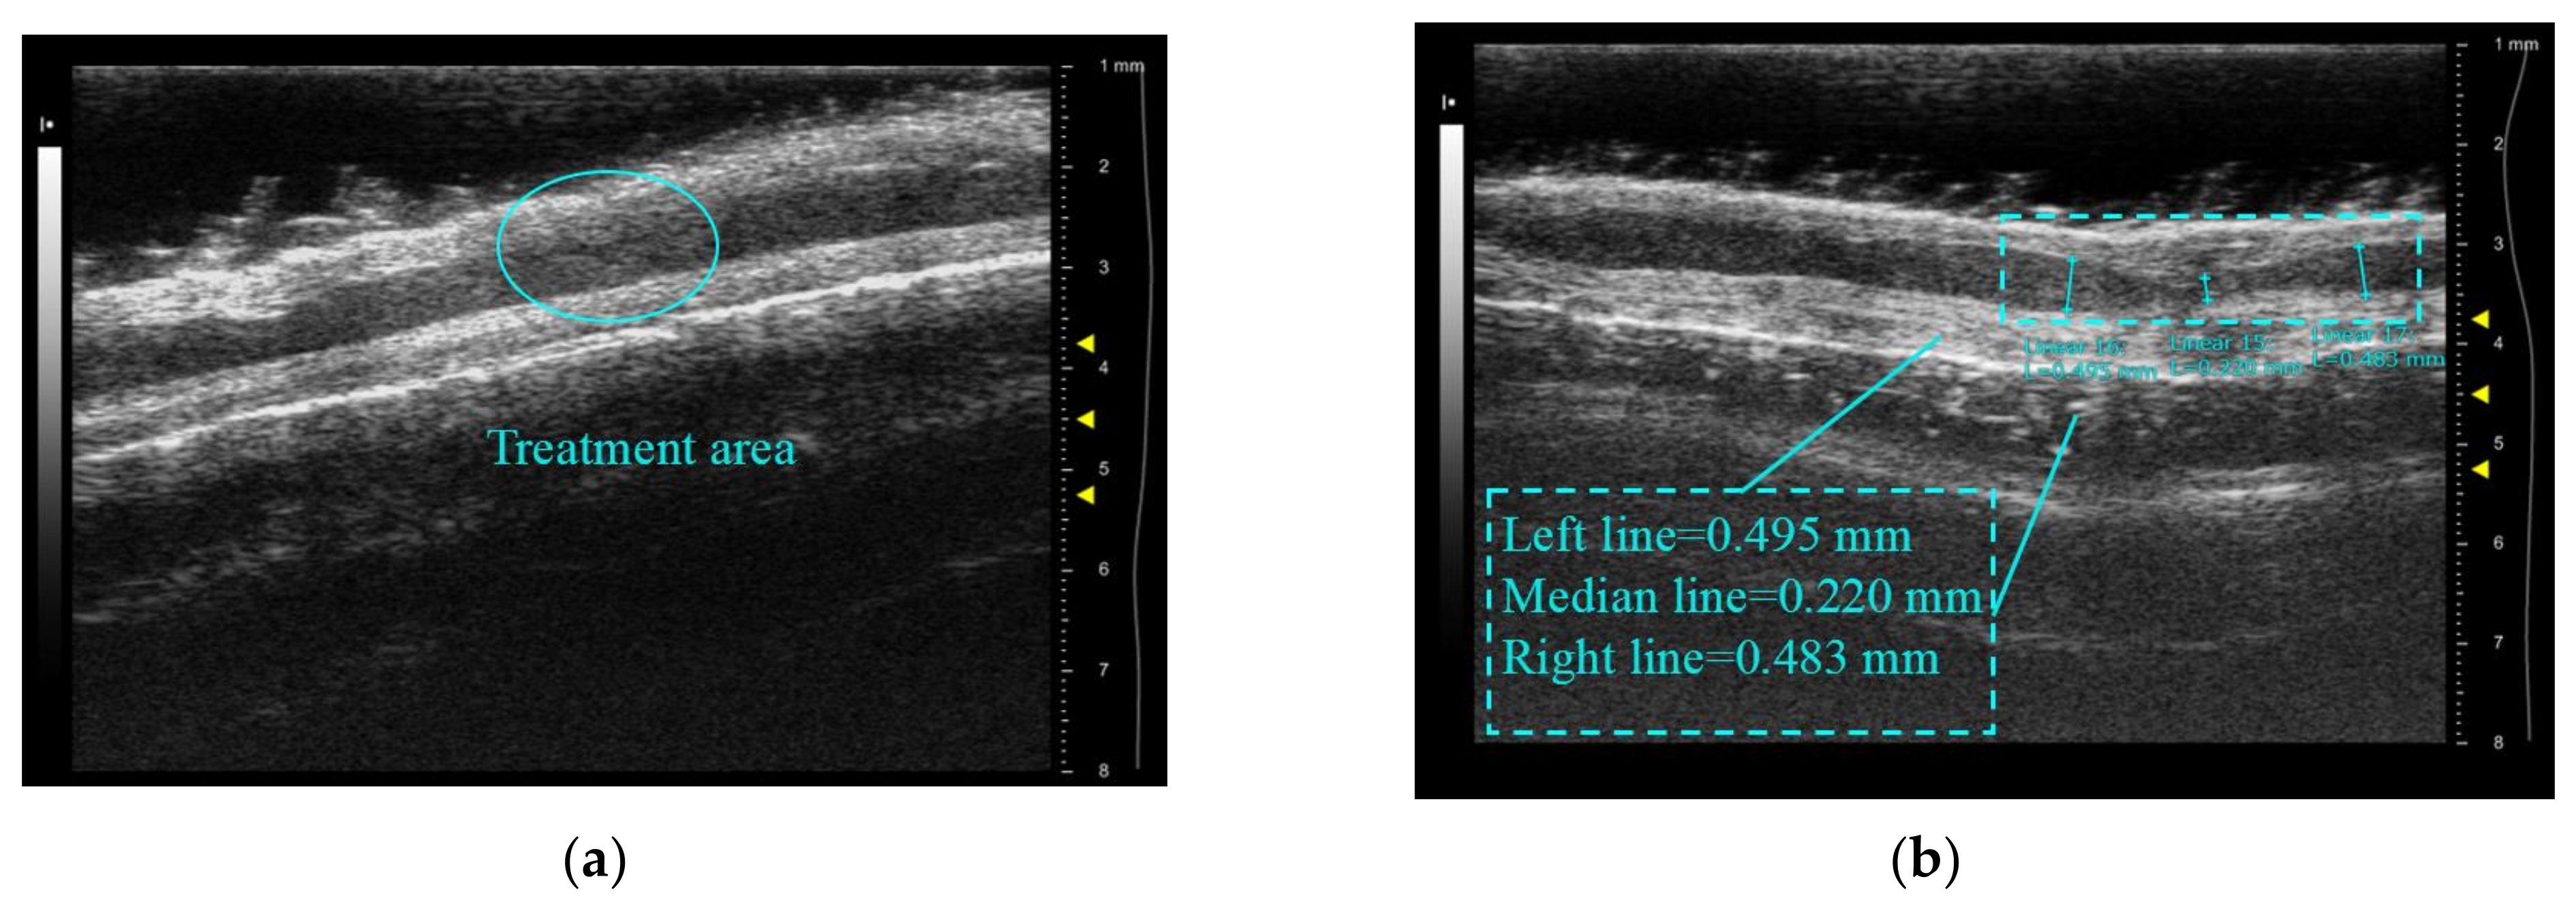

3.1.2. In Vitro Validation Experiments for Treatment Accuracy

Figure 12a shows the ear margin vein of the rabbit to be treated after fur removal, and Figure 12b reveals that the skin in the treated area is in a white degeneration state compared with other areas in the path of the vein. This indicates that the treatment area is limited to the vascular area and does not cause burning of the surrounding tissue. The white degeneration state is believed to be a type of skin burn. Figure 13a displays an ultrasound image of the marginal ear vein in an untreated rabbit ear, while Figure 8b shows the same vein after treatment. Contraction and deformation of the blood vessel wall can be observed at the treatment point in Figure 13b. Furthermore, the internal diameters of the blood vessels were measured using the built-in measurement system of the Vevo 2100. The diameter of the untreated area was approximately 0.49 mm. After treatment, the blood vessel contracted to 0.22 mm, and the shrinkage rate was approximately 55%, which is consistent with the observed vascular degeneration results in Figure 12b. This confirms the accuracy of the treatment.

The contrast image of rabbit ear vein contraction: (a) before treatment; (b) after treatment.

In in vitro validation experiments, due to the small size and slow blood flow speed of the rabbit ear margin veins compared to human veins, the temperature rises in the area quickly, and contraction of the superior and inferior vascular walls is observed. It is also found that if the treatment power is increased to pursue fast treatment, not only would the tissue and skin near the blood vessel be burned, but also the blood vessel would be directly ruptured and cause massive bleeding. Further research and consideration are needed to balance the treatment power and adopt appropriate cooling measures to protect the skin from burns.